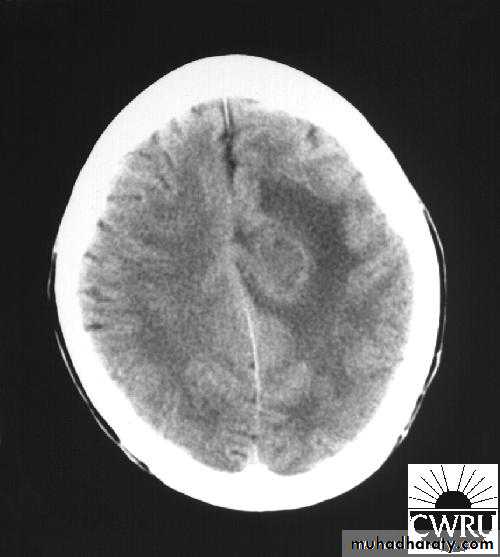

Brain Abscess CT without contrast

Brain Abscess CT with contrast

• They will show a single (or multiple) space occupying lesion that is well delineated with an enhancing wall, with variable surrounding oedema.

• B. Radiological Investigations:• CT or MRI is the investigation of choice.

• CT Brain is performed with and without contrast.